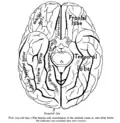

Базальная поверхность мозга, прямая извилина отмечена в верхней части